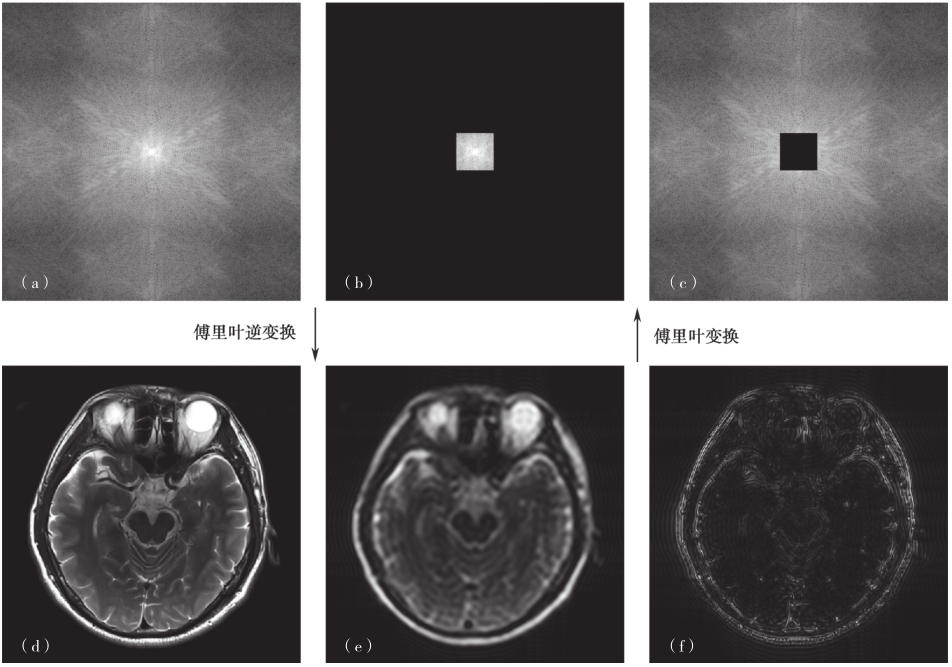

通过上述关系式我们可以发现k空间的两个重要特性:①k空间点阵中每一点对应不同的基波,包含有扫描层面的全层信息,重建过程可以理解为对基波进行加权累积(离散情况就是对基波的加权求和);②k空间中心区域的基波波长较长,外围区域的基波波长较短。因此,中心区域的磁共振(MR)信号主要决定图像的亮度、形状和对比度等低频信息,而周边区域的磁共振信号主要决定图像的细节和边缘等高频信息,效果如图3-1-3所示。

图3-1-3 k空间信号(幅值)和磁共振图像对应示意图

(a)k空间信号;(b)中心区域的信号;(c)外围区域的信号;(d)原图;(e)仅用中心区域信号的重建结果;(f)仅用外围区域信号的重建结果。